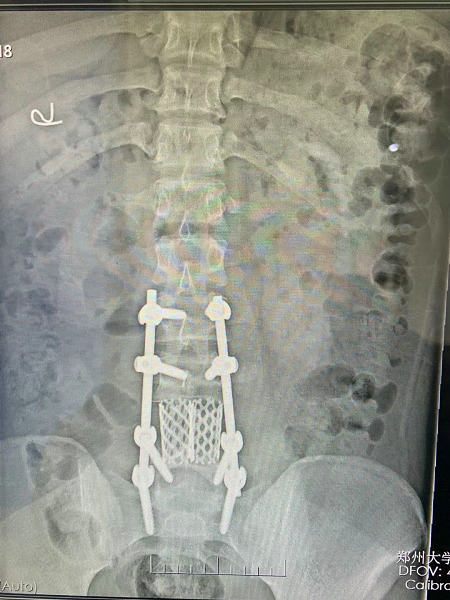

▲ 手术后(切除瘤体及第四腰椎)